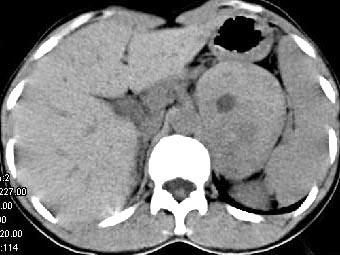

问题 女,36岁,无任何症状,体检时超声发现左侧肾上腺区占位,CT扫描如图所示,应诊断为 ( )

选项 A、左肾上腺髓样脂肪瘤 B、左肾上腺转移瘤 C、左肾上腺囊肿 D、左肾上腺嗜铬细胞瘤 E、左肾上腺腺瘤

答案 E